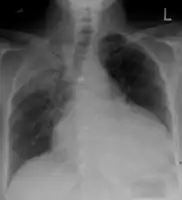

The so-called "water-bottle heart" is a radiographic sign of pericardial effusion, in which the cardiopericardial silhouette is enlarged and assumes the shape of a flask or water bottle.

Pericardial effusion due to malignancy. Note bulbous heart and primary lung cancer in right upper lobe.